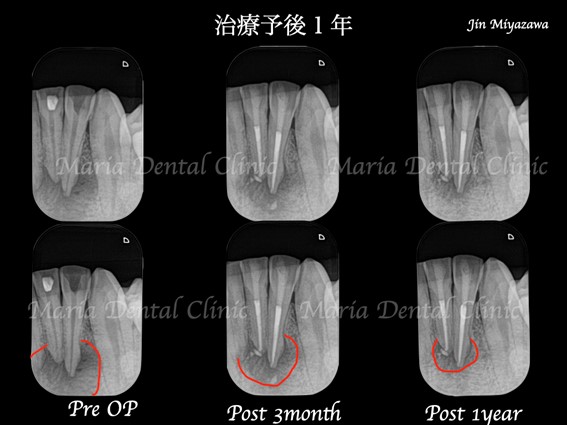

来院時には下顎は大きく腫れ、初診時のレントゲン写真(右側写真)ではレントゲンフィルムに収まりきらないほど病変が増大しており、確認のために撮影したC T画像(左側写真)では隣在歯(隣の歯)にまで及ぶ病変が骨を溶かしているのが確認できました。

3ヶ月後の経過では歯肉の腫脹、痛みは確認できず、レントゲンでも病変の縮小が確認できたことから1年間隔で経過観察をおこなっております。

術後1年経過し、根尖性歯周炎は治癒傾向を示していることから再度1年後に経過観察を行う予定です。